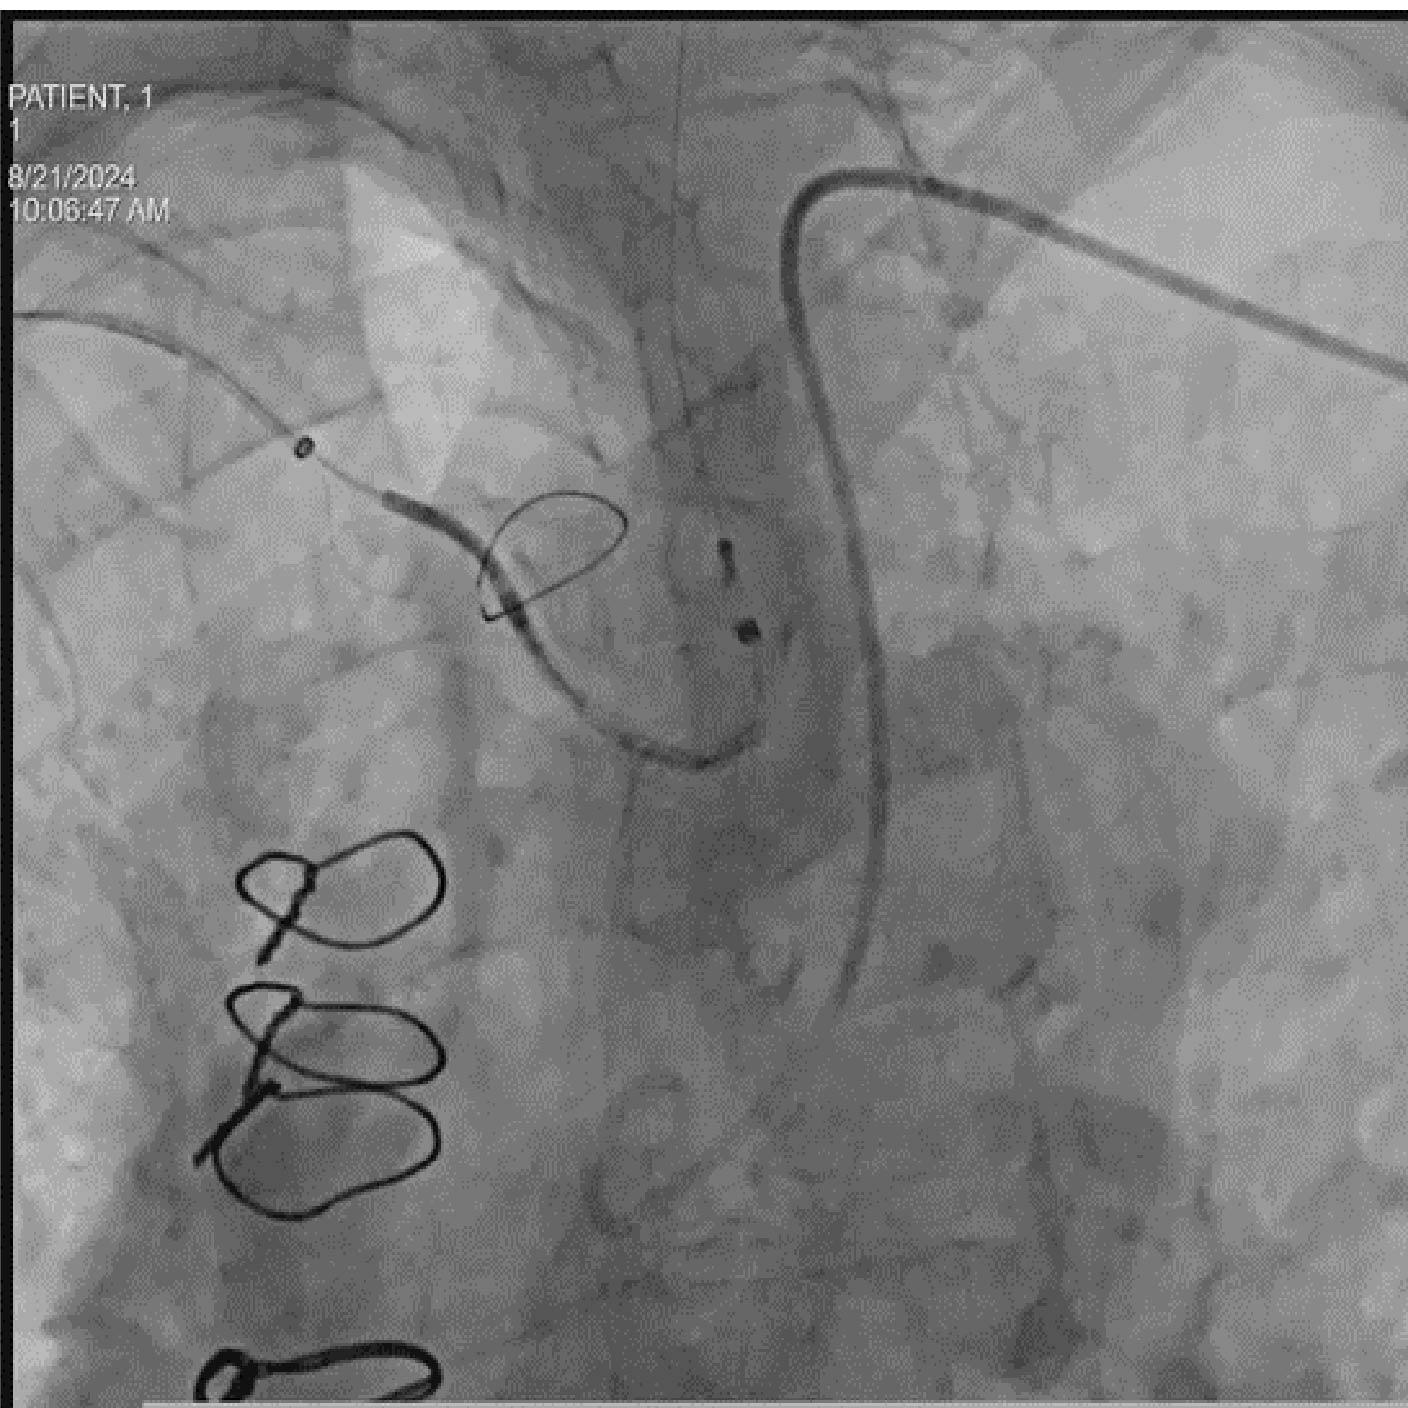

Posicionamiento y despliegue del dispositivo

Objetivo clínico: Soporte para la colocación de un dispositivo de protección cerebral como herramienta para mitigar el riesgo de accidente cerebrovascular embólico.

Soluciones y características seleccionadas: ARTIS pheno, Case Flows, Una combinación preestablecida de configuraciones (angulación, disposición de la pantalla, etc.), personalizada para la colocación del dispositivo SENTINEL™*, reduce las interacciones con el sistema. Con Case Flows, una única interacción del usuario reemplaza el ajuste de hasta 6 configuraciones del sistema³. syngo 2D/3D Fusion - Aplicación para superponer la anatomía de la arco aórtico basada en tomografía computarizada sobre fluoroscopia en vivo, para apoyar la navegación del dispositivo. Se ha demostrado que la guía por fusión reduce significativamente el tiempo de despliegue del dispositivo SENTINEL™* y el uso de contraste⁴.